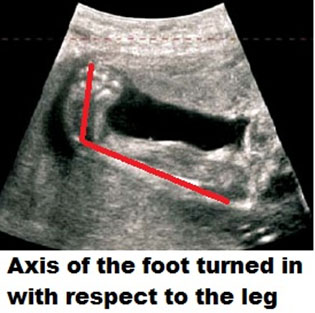

Presently, many clubfeet are recognized in utero during prenatal Ultrasound screening. It is an eminently treatable problem, and there is no need for anxiety for parents and individuals in its management.